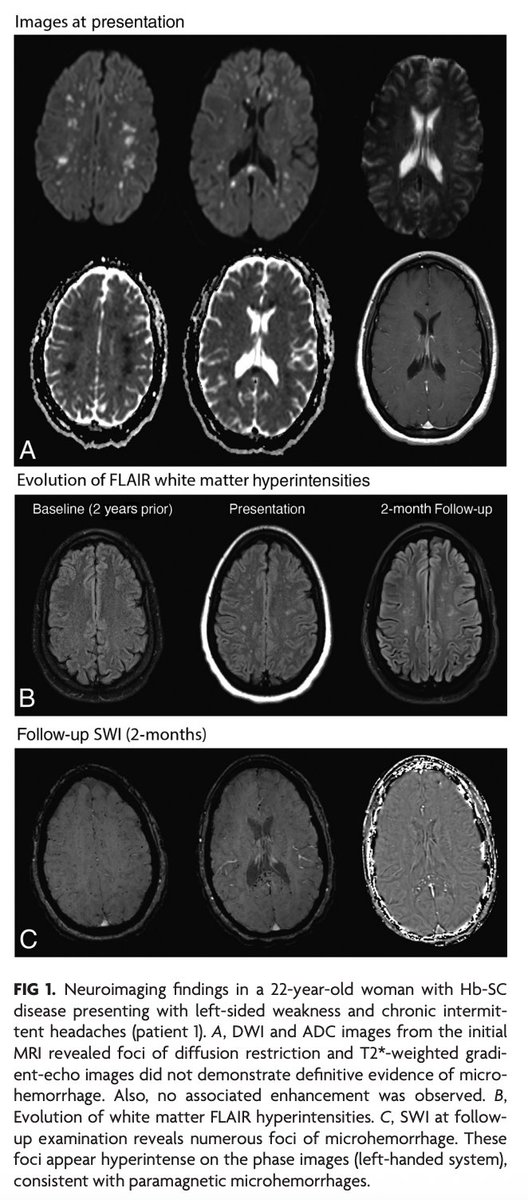

@Rshnzr @HosseiniHelia @zack4186 "CFE in sickle cell–related hemoglobinopathies is more common in complex hemoglobinopathies with otherwise milder disease course and is typically more fulminant compared with traumatic CFE. MRI findings follow a pattern with scattered foci of restricted diffusion, known as the

"Nontrauma-Associated Cerebral Fat Embolism Syndrome in Sickle Cell–Related Hemoglobinopathies: A Case Series and Systematic Review" https://t.co/mjcZ5AQXte

#FellowsJournalClub

@Rshnzr; @HosseiniHelia; @zack4186